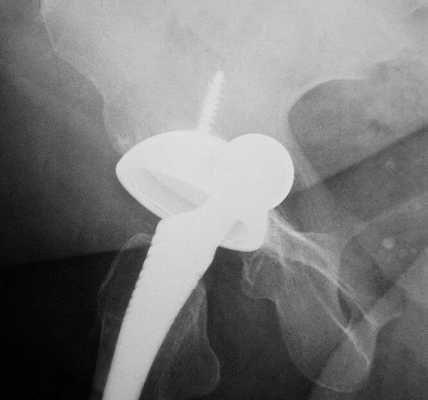

Диагностика нестабильности протеза

При наступлении первых симптомов нестабильности эндопротеза тазобедренного сустава либо до появления таковых не будет лишним пройти курс диагностических мероприятий. Врач назначит следующие виды обследования:

- рентгенологическое исследование тазобедренного сустава;

- проведение анализа состояния костной ткани и ее плотности с помощью метода денситометрии;

- анализ процессов метаболизма в костной ткани.

В некоторых случаях назначение перечисленных выше мероприятий происходит сразу же после хирургического вмешательства. Особую опасность представляет изначальное наличие у пациента остеопороза, так как именно данная особенность костной ткани может спровоцировать нестабильность протеза после установки.